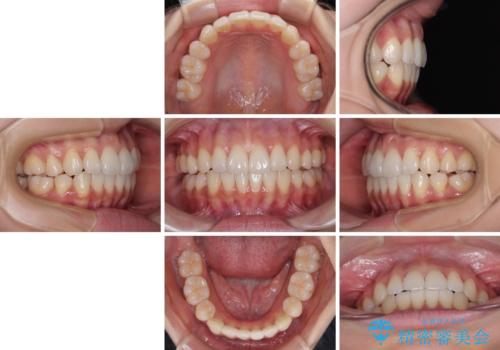

1. 開始前

2. 治療途中

3. 終了時

1. 抜歯矯正の軽度後戻りを解消 インビザライン矯正の治療前

2. 抜歯矯正の軽度後戻りを解消 インビザライン矯正の治療中

3. 抜歯矯正の軽度後戻りを解消 インビザライン矯正の治療後